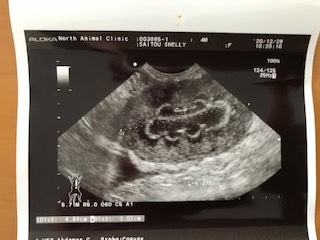

12月24日のクリスマスイブに再受診したところ、腹部エコーで臓器の周辺の異常(臓器周囲の炎症:写真)腹水貯留が認められ、また、肝機能障害と黄疸、高度な貧血(Hb4.5)、体温41度、などからFIP(猫伝染性腹膜炎)の可能性が高いとのことでした。また確定診断のための血液検体でPCR検査をしました。(その後、12月29日に陽性と判明しました)

内臓のエコー写真:臓器の周りが白く映っており、肉芽腫のようだと説明されました